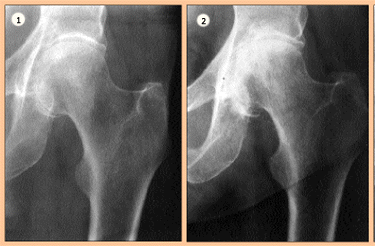

Mise au point Coxarthrose destructrice rapide , J. Blanchard Service d'orthopédie et traumatologie de l'appareil Locomoteur - Lausanne , P.-F. Leyvraz Service d'orthopédie et traumatologie de l'appareil Locomoteur - Lausanne N°73 - Avril 1998 ● 11 min de lecture